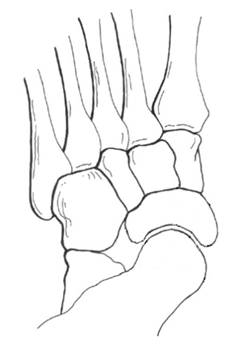

多趾征 – 从正后方观察患足,如果外侧缘看到超过两个以上的足趾,则提示多趾征阳性

前足外翻角 – 检查者一只手纠正足跟外翻。 – 检查者另一只手稍稍用力,支撑前足,纠正跖楔关节对前足内翻角的影响

跟骨外翻角 – 患者站立位,取跟腱轴线以及跟骨轴线为角的两条边,取距骨结节位置为角的顶点,测量跟骨外翻角。 |